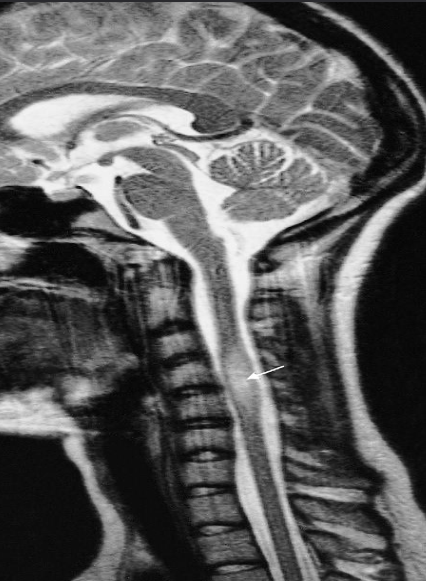

Sagittal T2 MR - Syringomyelia

young adult women with optic neuritis

T2 -weighted MRI showing a plaque of demyelination (arrow) in a patient with multiple sclerosis

Cervical disk herniation

MRI cervical spine (T2-weighted; sagittal plane) of a

patient with symptoms of cervical myelopathy

A herniated disk at C5–6 effaces the dural sac and compresses the spinal cord. Hyperintense compression-induced edema is seen within the cord